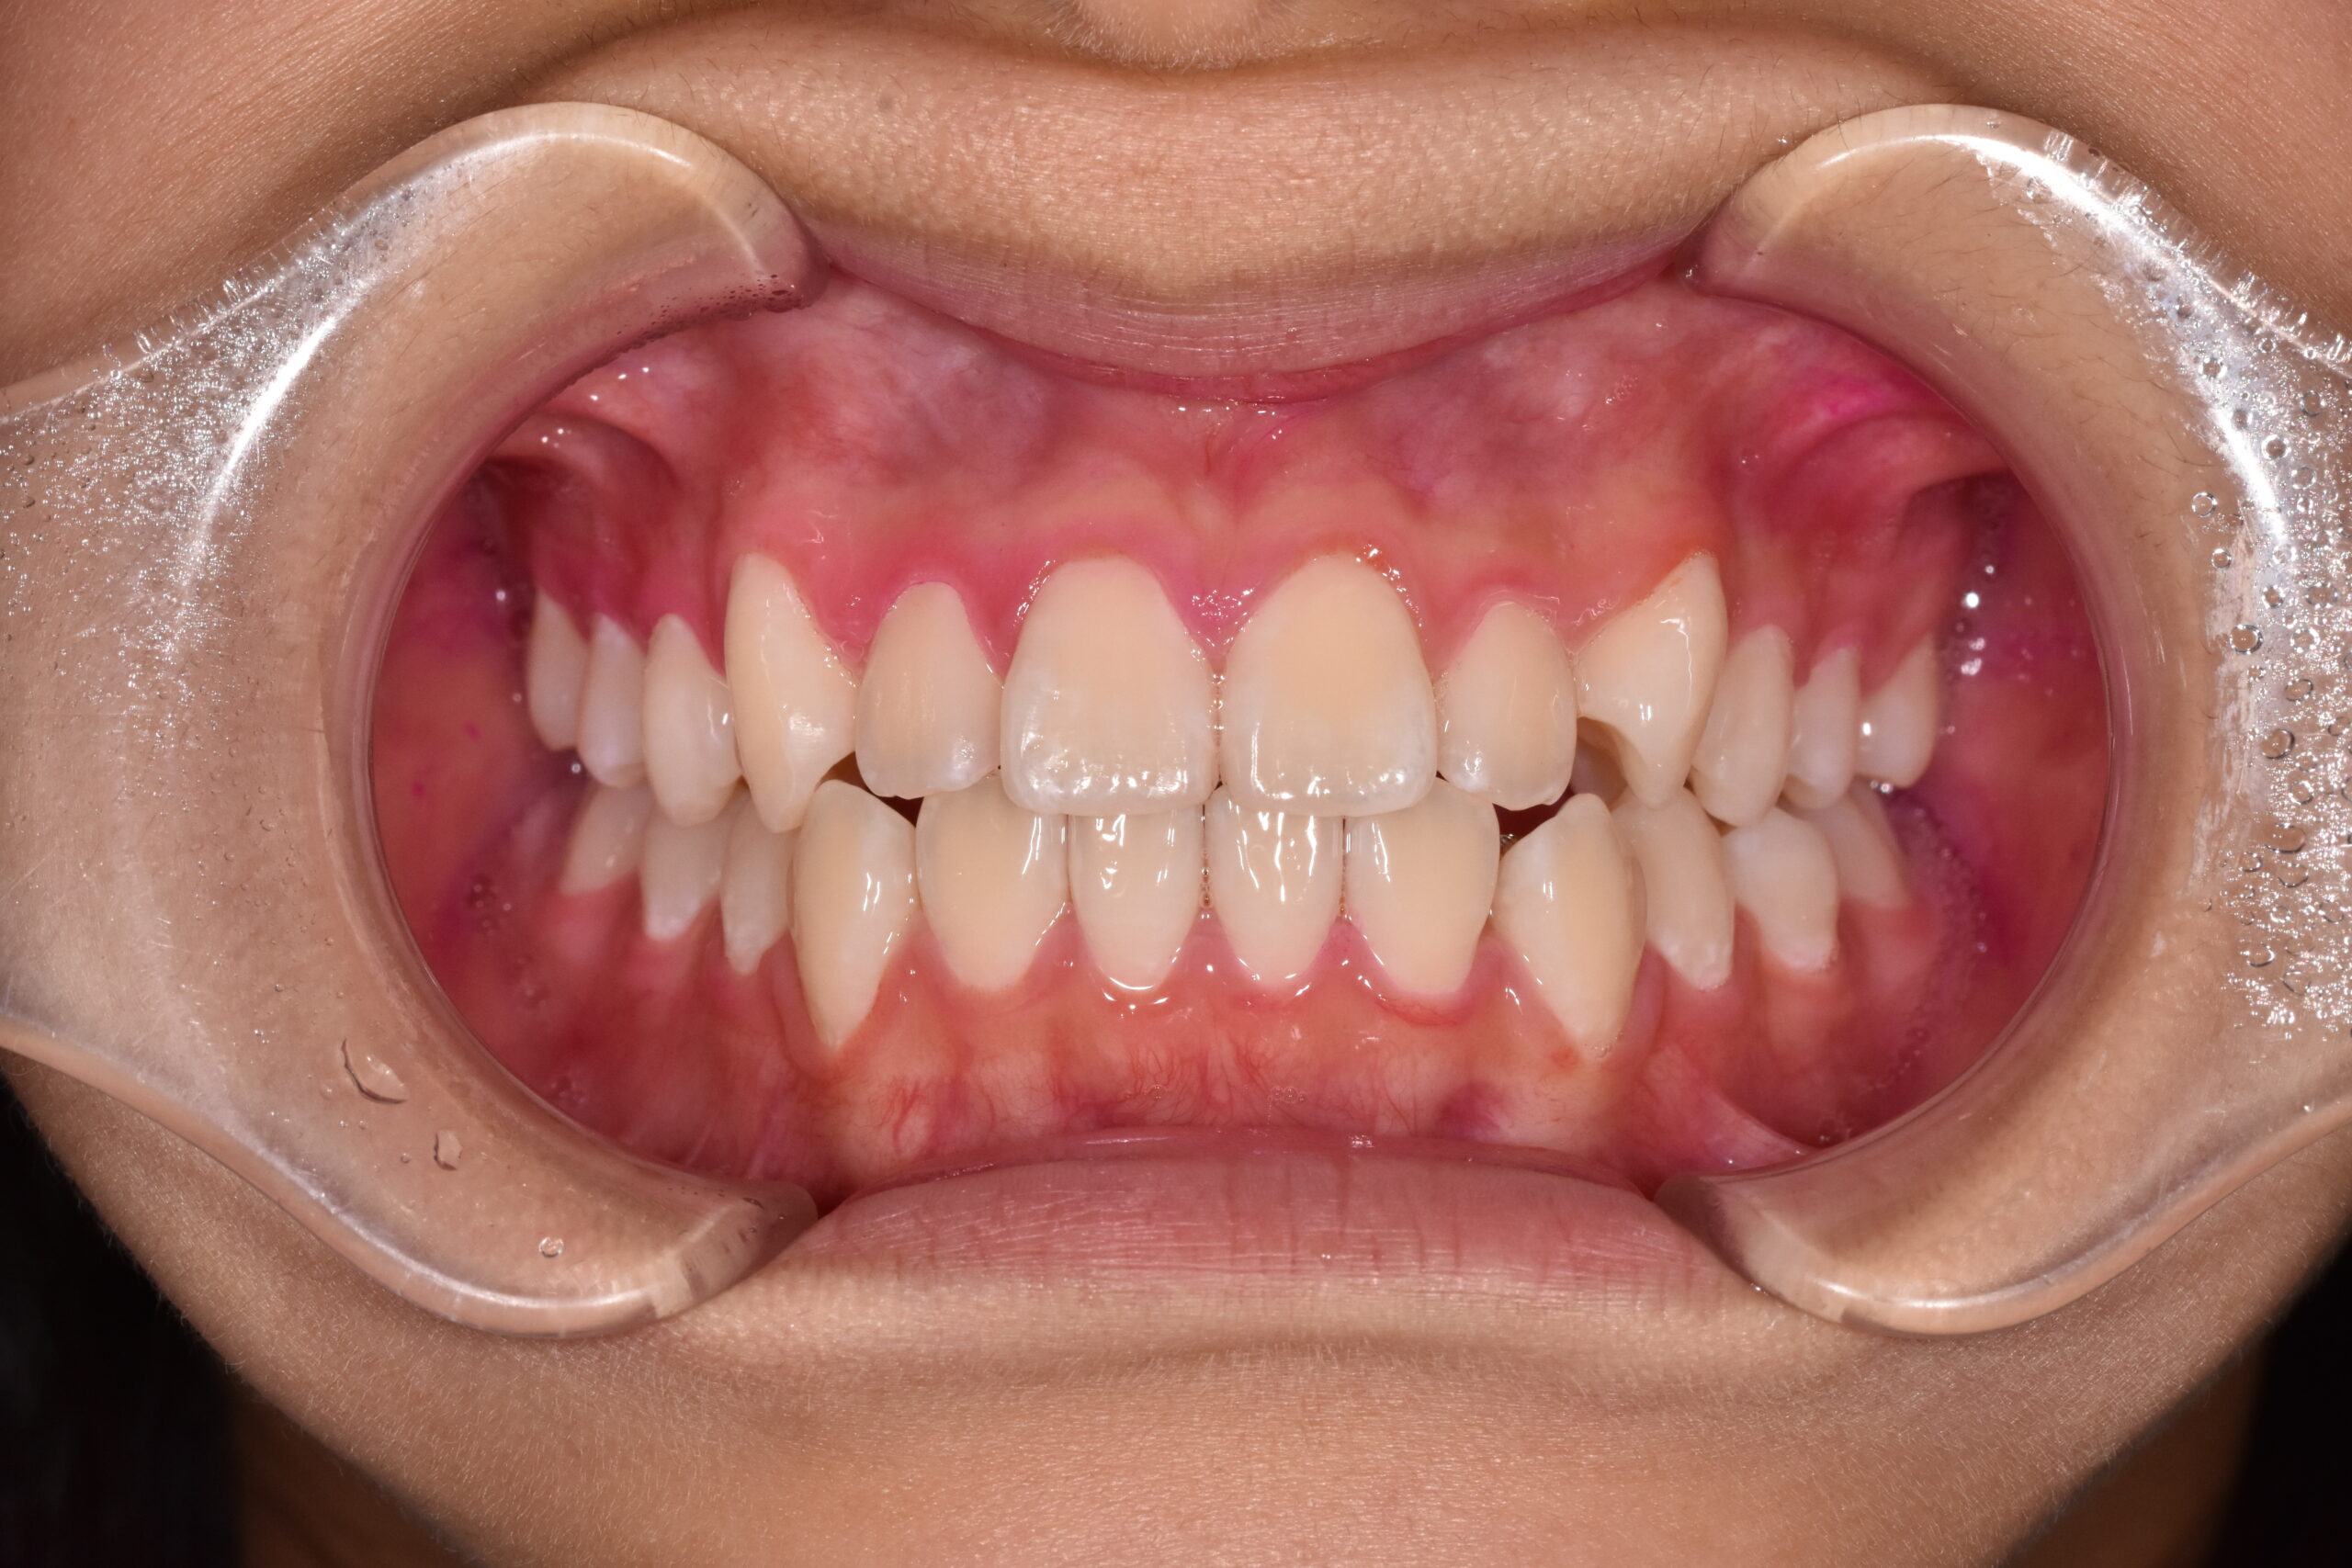

治療後